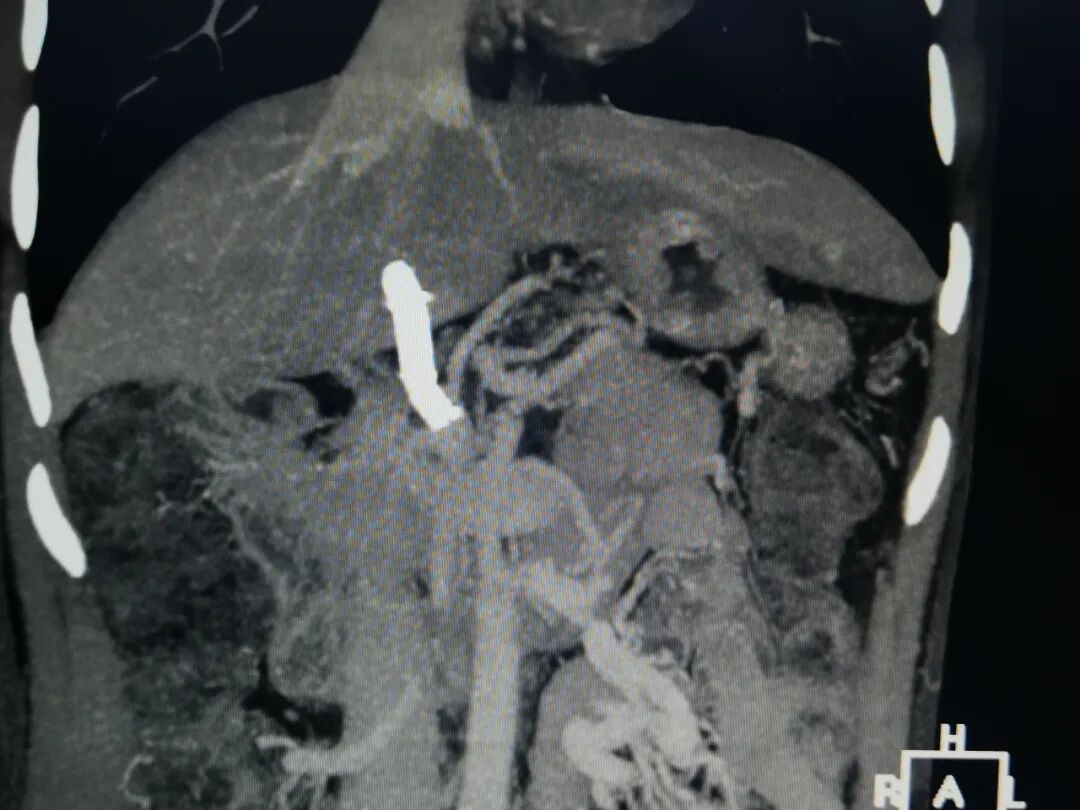

诊断:肝炎后肝硬化,门静脉海绵样变,肠系膜上静脉血栓形成,肝功能B级。

盆腔CT显示:左髂总静脉压迫。

8. 置入8*50mm覆膜支架建立门静脉下腔静脉分流道。造影提示:分流效果满意。

患者进食正常,无腹痛。无肝性脑病。一月后体重增加10Kg。门静脉CTV:分流支架通畅。